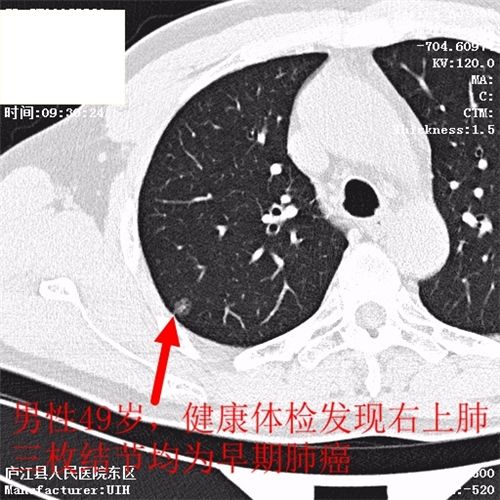

肺癌目前发病率排名第一,肺癌5年生存率任然低于20%,为什么会这么低?就是发现肿瘤时就是晚期肺癌,晚期肺癌无论是手术还是放化疗治疗效果就会差很多。如何能够早期发现?目前国际上达成专家共识,那就是低剂量螺旋CT检查,通俗易懂地说就是接受最小的辐射剂量,达到最好的早期肺癌的诊断效果,要知道,早期肺癌是不痛不痒,没有任何症状的,要想查出它只有CT检查,照张胸片那就意味着是“凶片”。胸部低剂量CT让早期肺癌无处逃遁!

图片展示:健康体检中发现的肿瘤